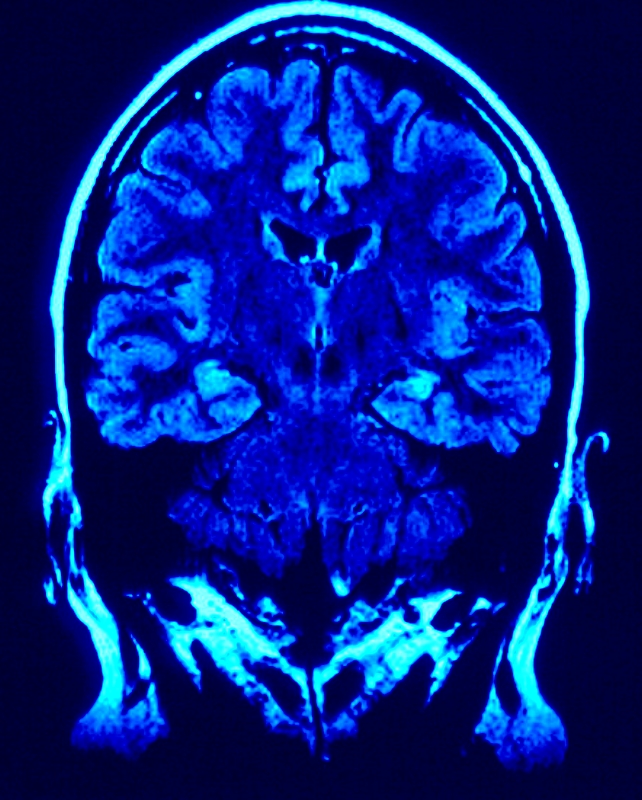

Pour autant, l’hypnose est un phénomène bien réel et, même si les mécanismes précis en sont encore méconnus, il faut distinguer deux types d’hypnose : celle qui provoque une perte de connaissance et une absence de conscience du sujet, et celle qui permet la relaxation, la parole et l’écoute dans un état de calme favorisé par une oxygénation et un ralentissement du rythme cardiaque. Dans les deux cas, il se passe quelque-chose au niveau de la capacité d’action. Mais, plutôt que de chercher du côté des ‘effets’, intéressons-nous à la typologie du lien qui s’établit entre l’hypnothérapeute et le sujet.